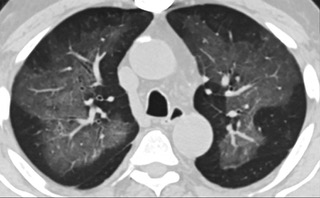

疑點(diǎn)一,電子煙患者的CT影像和臨床表現(xiàn)并不具有特異性。所謂美國(guó)電子肺炎患者,其實(shí)是對(duì)沒有其他合理診斷證據(jù)、吸食電子煙肺炎患者的統(tǒng)稱。這些患者在病發(fā)前90天內(nèi)吸食了電子煙,尤其值得注意的是,部分患者的CT影像特征和臨床表現(xiàn)與病毒性肺炎患者極其相似。

中、下肺軸位CT平掃顯示毛玻璃樣混濁伴胸膜下保留。(同一病人CT影像)